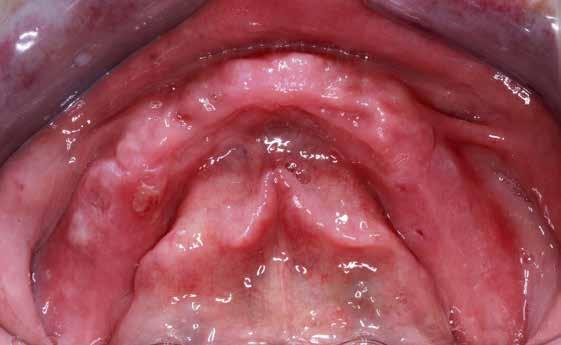

Ebben a cikkben egy 16 éves lánypáciens esetét szeretném bemutatni (1–7. képek)

A Pitts21-es fix készülékes kezelés során a harapásemelőket a felső nagyőrlő fogakra ragasztottuk, hogy a felső molárisok intrúziójával segítsék a harapás zárását (8. kép) Ún. keresztharapásos, majd később normál class 2-es gumihúzással (9–10. képek), továbbá az elülső fogakon alkalmazott ún. Rainbow harapás-záró gumihúzással (11. kép) korrigáltuk a jobb oldali teljes premolárisnyi distal-harapást, valamint az elülső nyitott harapást.

6 hónap után a nyitott harapás már nagyjából összezárásra került (12. kép)! A gumihordás a kezelés teljes hosszában folyamatos, éjjel-nappal, 22-24 órában az étkezések és az utánuk történő fogmosás kivételével.

A fix fogszabályozó készülék mindössze 16 hónapos kezelés után került eltávolításra! Páciensünk legnagyobb örömére állcsontműtét nélkül sikerült mind az arcesztétikai, mind a funkcionális rehabilitáció (13–18. képek)